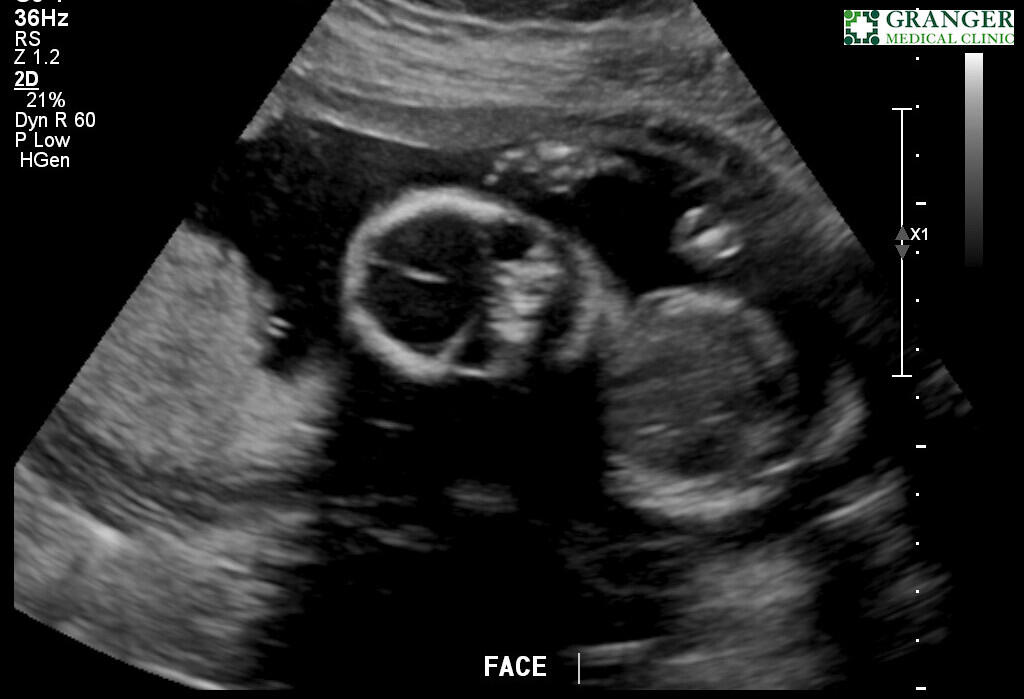

Ultra sound @ March 25th

It has only been three months and three weeks since we found out we are having a child.Since then, we have gained a bassinet in our bedroom and a closet filled with new baby clothing. New artwork for our nursery and overall has been the subject of conversation every single day since.It is sufficient to say that our lives have changed forever.Having this drastic a change in such a short time has come with much stress and complications, and almost all aspects of our lives.Most surprising are the emotional changes we have undergone over the past three months. As it turns out, (from parenting books and colleagues’) husbands and wives will go through drastic hormonal changes while the wife is pregnant.All this has led to a lot of planning for our future baby. There are times when I feel more stress than I've ever felt in my entire life.However, in the same breath, I believe I have also felt the most gratitude and love for my family that I have ever felt.For sure, things are differentBut overall, despite all the sleepless nights and worrying about our baby’s future, I’ve been able to see the world in a different, more positive light than ever before.Abree and I have been dreaming of this moment and have been planning for our new child. Now that it is here, it feels almost surrealWe are very excited